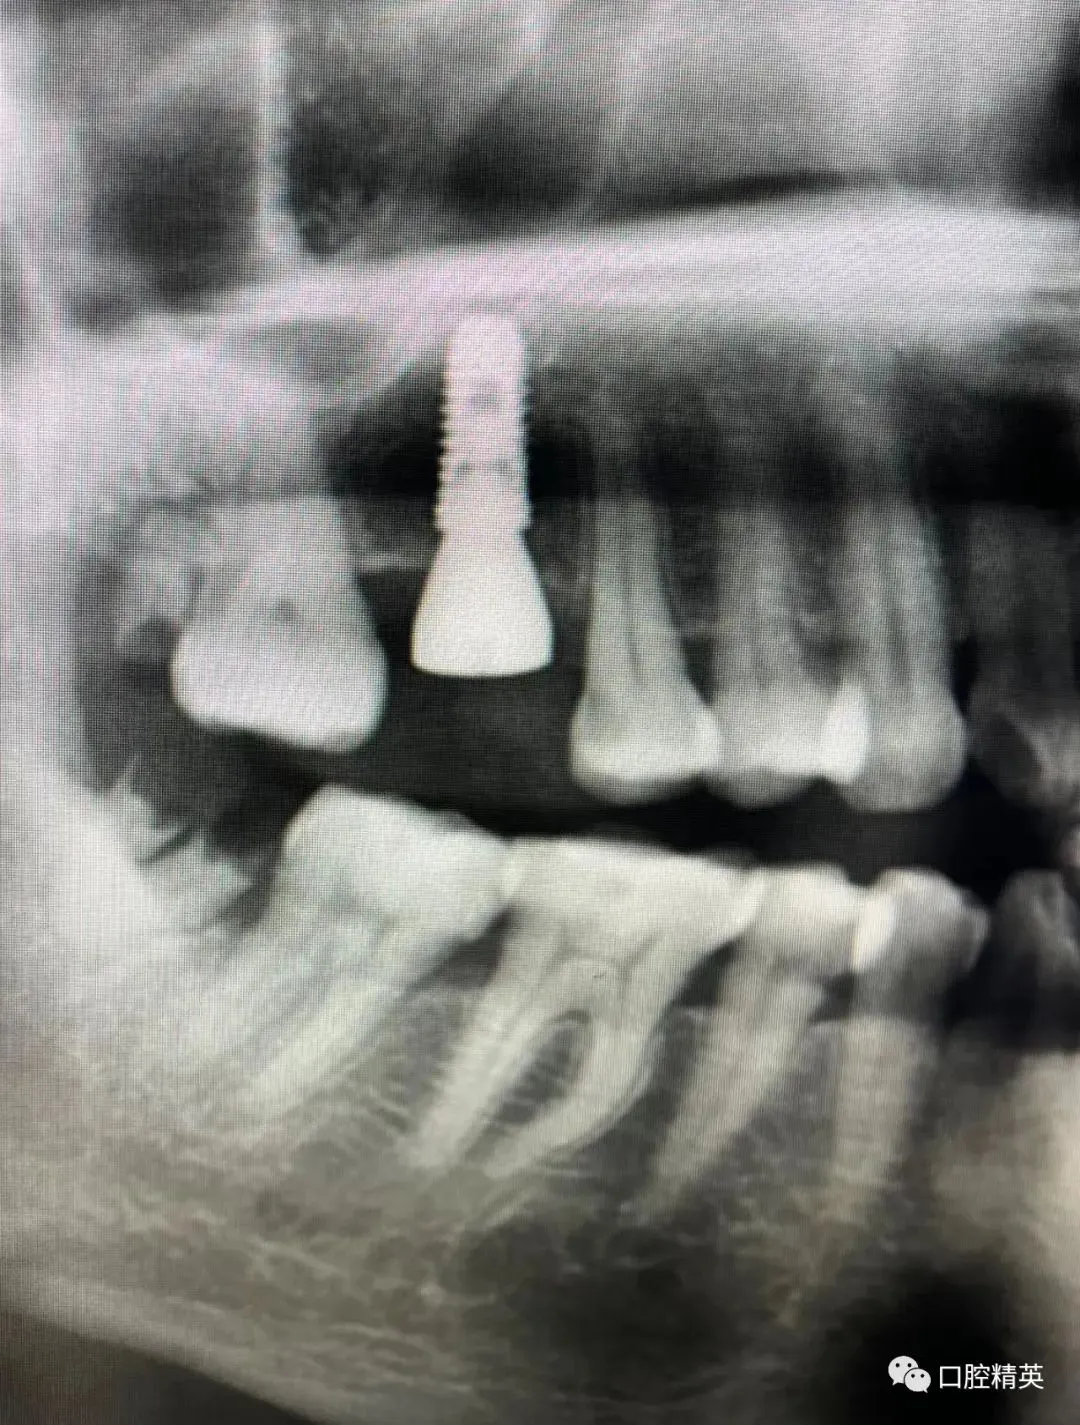

7、种植影像学分析;可以获得骨高度 ,骨宽度信息 ,甚至可以模拟种植体植入位点

六、学员回家后部分病例